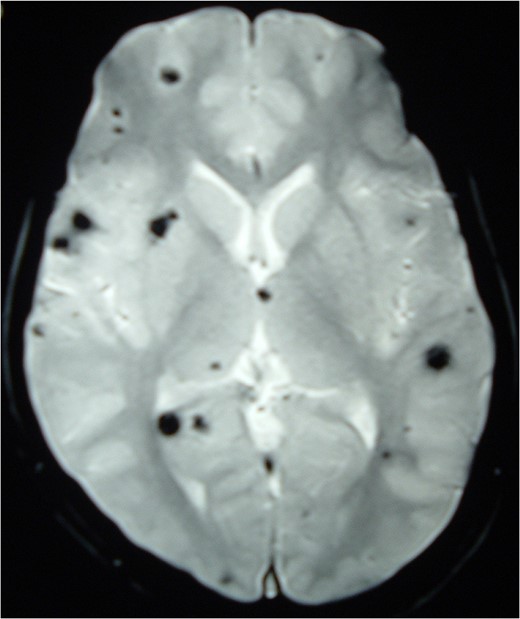

MRI Brain (GRE T2WI) showing multiple hypointense lesions diagnosed as cerebral cavernomas.

Intramedullary spinal cavernomas may be associated with multiple concurrent occult cerebral cavernomas as seen in our case. This makes MRI of the complete neuraxis a crucial next step [1, 4, 5]. Familial CM syndrome should be suspected for any case with multiple cerebral cavernomas [4]. MRI remains the gold standard for diagnosing both cerebral and intramedullary cavernomas. They appear as mixed signal intensity lesions in on T1 and T2-weighted images surrounded by a low-signal intensity zone (due to hemosiderin deposits) best seen on T2-weighted images [4, 5, 8].